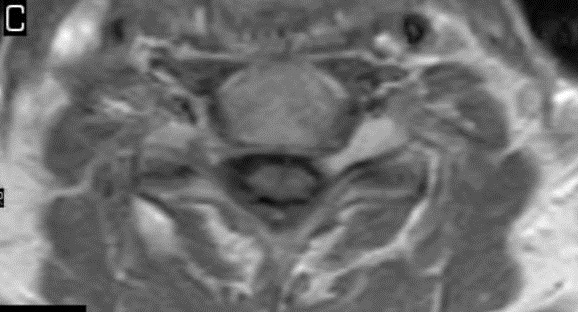

I have provided some select images from the MRI study that was obtained. Initially, the study was ordered non-contrast. Fig. 1 is a midline T-2 weighted image. It demonstrates a degree of posterior disc bulging at C6-C7. No focal posterior discal prominence was noted that would indicate a herniation. Fig. 2 is a gradient echo weighted image through the C6-C7 disc space. In this image, there is obvious expansion of the left intervertebral foramen with a degree of erosion of the facet at the posterior margin of the foramen. The signal intensity is bright on this image, compared to the normal intermediate signal intensity noted within the right foramen. You will note a degree of irregularity at the posterior margin of the disc in this cut, consistent with the disc bulging seen on the sagittal images. There is not sufficient encroachment of the central canal however to account for a neurologic deficit. A left parasagittal STIR image (Fig.3) reveals an obvious focus of abnormal signal within the left C6-C7 IVF that corresponds to the finding that was noted on the axial image. The signal intensity of this area was high on the STIR, gradient echo, and T-2 weighted images, and low on the T1 weighted images, consistent with fluid. At this point what diagnoses would you entertain, and would you order any follow-up imaging or testing?

This patient underwent a second limited contrast examination. Pre- and post-contrast T-1 weighted images were obtained. Fig. 4 represents the pre-contrast T-1 weighted image, and Fig. 5 represents the post-contrast image at the same level. There is a quite definite increase in signal intensity of the mass on the post-contrast images. Thus, the mass is said to enhance and this is indicative of a neoplastic process. The most common extradural intraforaminal mass is a schwannoma, which represents a nerve sheathe tumor. This was the presumptive diagnosis as the patient underwent surgery for removal of the tumor. Subsequent biopsy of the lesion confirmed schwannoma. The patient did well post- surgery and the left upper extremity symptoms resolved.